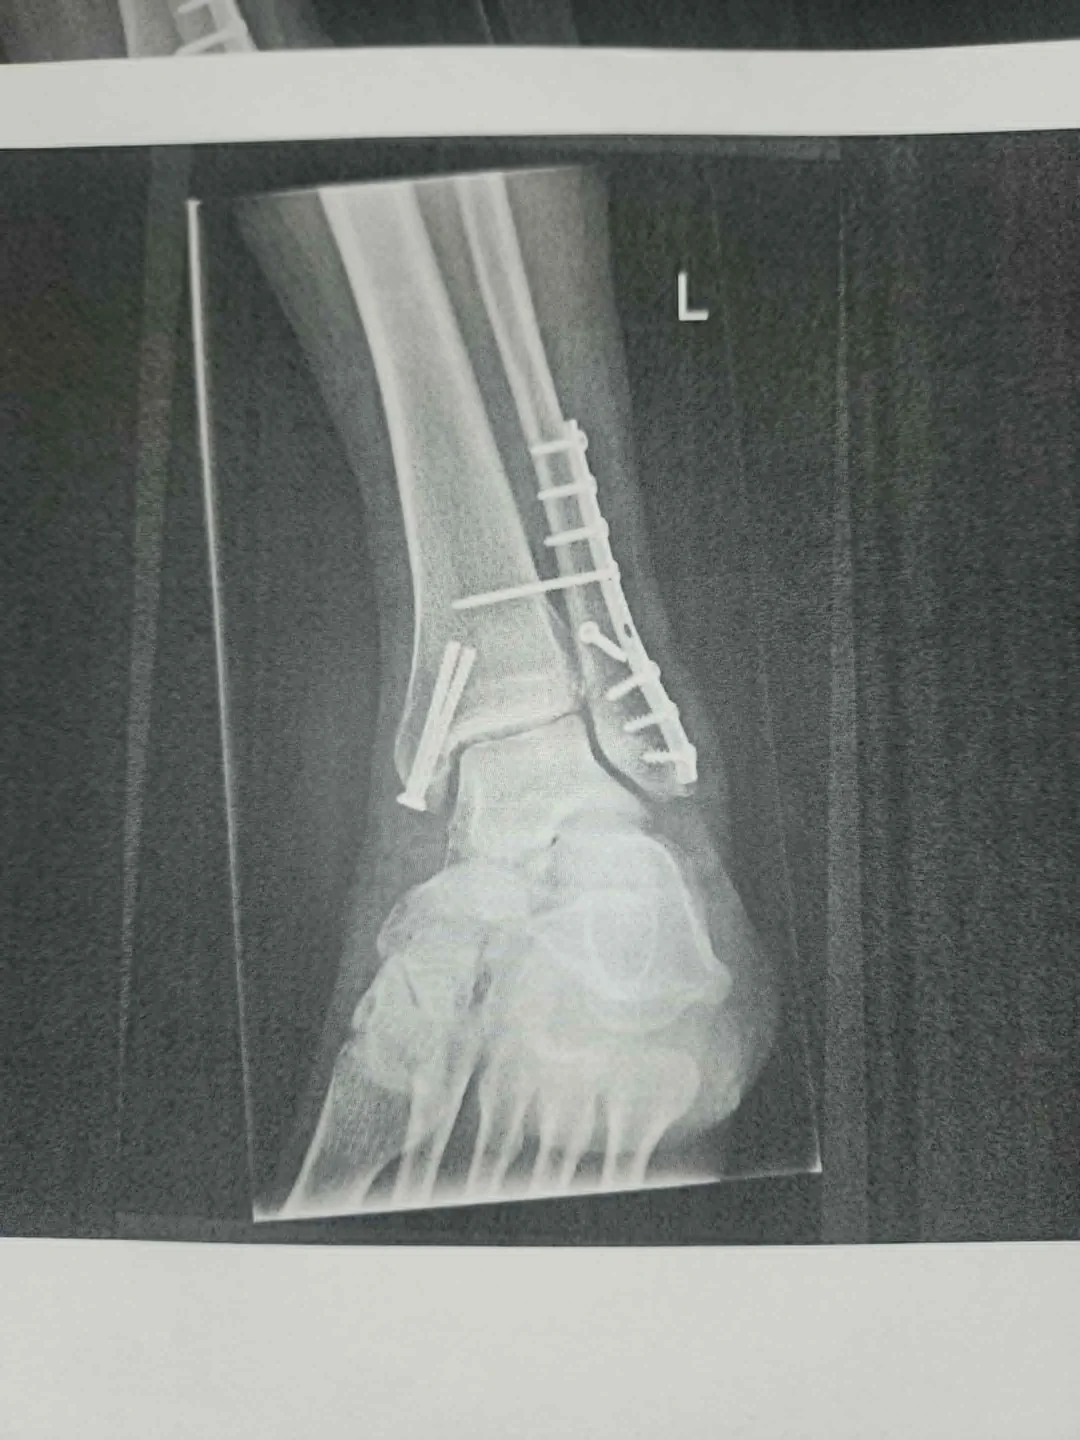

I’m in Cologne and fractured my ankle pretty badly five days ago — surgery, titanium plate, screws, the whole deal. I have a big boot and crutches and have to fly back to the US this Saturday. I’ve got wheelchair assistance booked and a doctor’s note saying I’m fit to fly, but I...